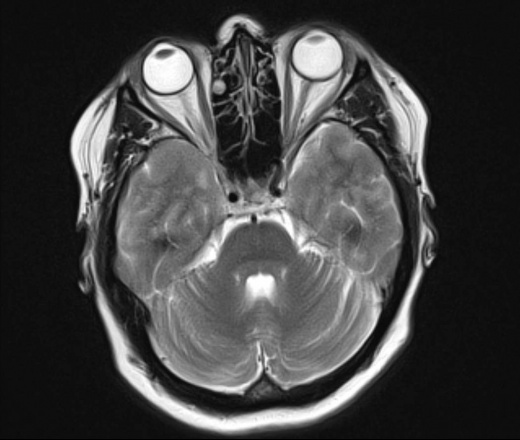

У пациентки 1960 г.р. с 2005 наблюдается птоз, диагноз миастении исключен. МРТ ГМ впервые выполнено в августе 2015 г в плановом порядке, новых жалоб не было, по описанию МРТ - очаговые изменения белого и серого вещества больших полушарий и ствола мозга - признаки энцефаломиелита.

В сентябре 2015 новое МРТ: субкортикальные очаги в белом веществе больших полушарий, не накапливающие контраст; уменьшение размеров ряда очагов - Данных за демиелинизирующее заболевание нет, поствоспалительные изменения. Консультирована в НИИ неврологии, предположено демиелинизирующее заболевание вторичного генеза. В неврологическом статусе: правосторонний птоз, ограничение конвергенции, асимметрия носогубных складок.

Сейчас вновь сделано МРТ, появлись 2 новых очага: в полюсе правой височной доли и поперечной височной извилине слева. Очаг в задних отделах левой теменной доли (угловая извилина) увеличился в размерах. С контрастом пока не работаем.

Подскажите, пожалуйста, что это за процесс? Поражено только белое вещество или серое также? Есть ли поражение ствола мозга?

Действительно, динамика отрицательная и на первичную демиелинизацию не тянет. Какой-то продолжающийся энцефалит, какой именно и гадать нечего, это не наше дело, навскидку можно написать длинный ряд типа Эбштейна-Барра и пр, всё требует серологического доказательства.. В стволе ничего не увидел. Поражено белое и серое вещество.